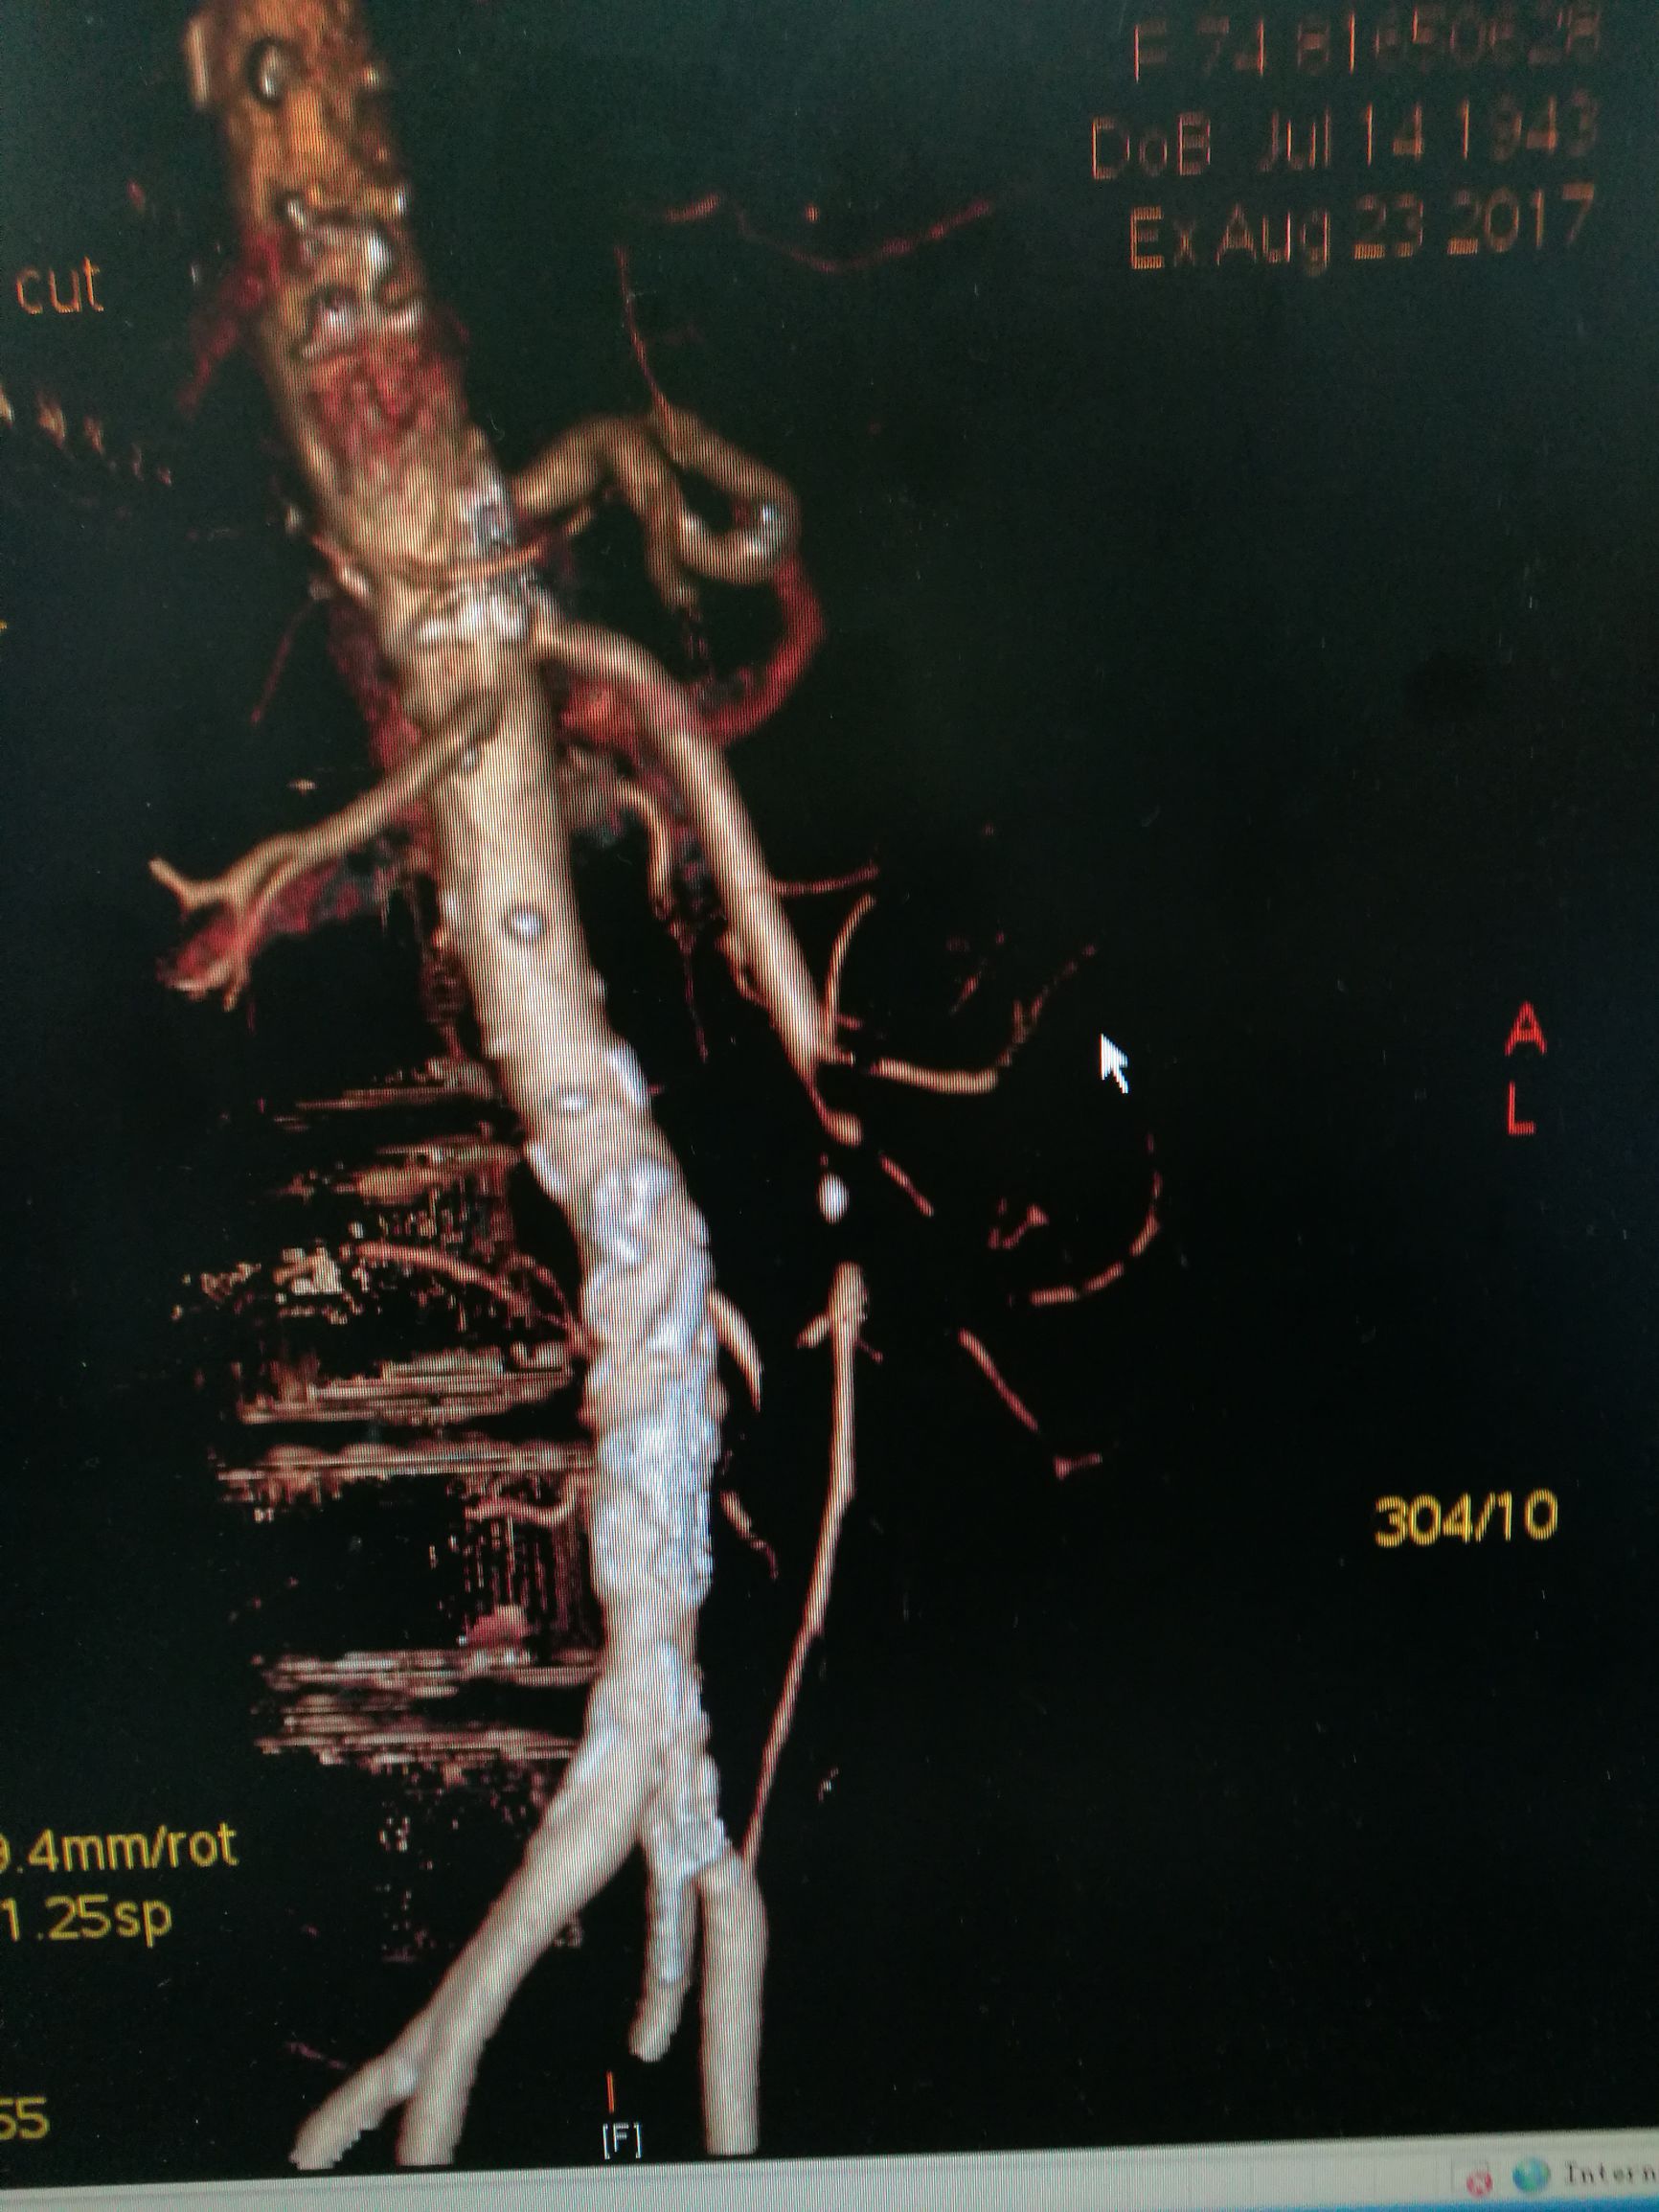

下一台手术室个急性肠缺血的患者。W奶奶近年74岁,突发腹痛14小时来我院看急诊。患者14个小时前突发腹痛,脐周为主,疼痛呈持续性,伴阵发加重,患者既往有冠心病,心脏搭桥病史。来看急诊,急诊医生很警惕,做了个增强CT,可见肠系膜动脉内充盈缺损(图1,2),诊断明确,考虑到患者高龄和心脏病史,决定先尝试微创治疗。

图2. 三维重建可见肠系膜上动脉中断